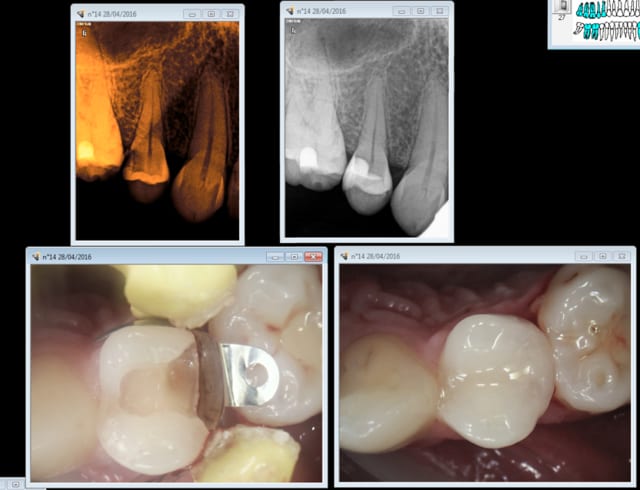

Et non je n'ai pas toujours un coeur de pierre. Coeur d'artichaut pour cette 14 qui aurait mérité que je m'occupe d'avantage de son cas je pense, on verra bien. -)

J'ai entendu son appel : pitié laisse moi vivre. -)